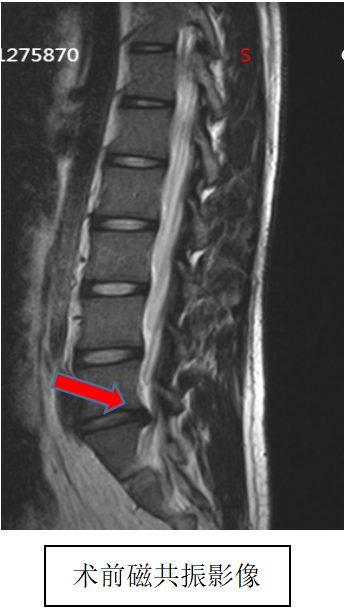

吴静晔主任是北京积水潭医院派驻郑州医院的脊柱外科专家,也是北京积水潭医院郑州医院脊柱外科的执行主任,在为小明做了全面检查后,结合术前 MRI 精准定位病变部位,在充分沟通诊疗方案与风险后,为小明实施了微创手术,精准解除神经压迫。

术后即刻复查磁共振显示,手术达到预期效果,小明的疼痛快速缓解,麻木感逐渐消退,终于能正常坐立、平稳走路。